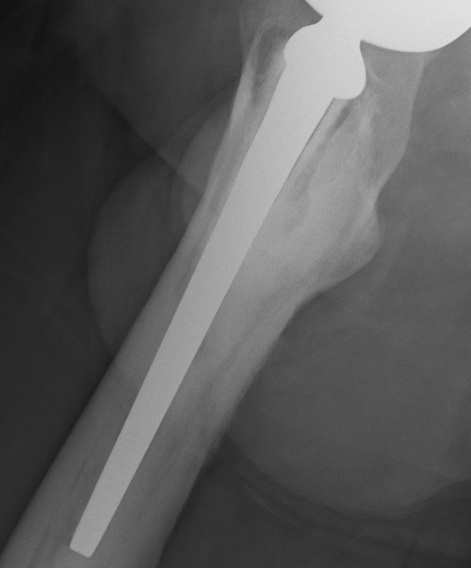

- Signs of movement of the femoral stem of the hip implant – lines down either side and possible bone damage – the cement contains ceramic and this can then act as a grinding past as the stem moves. This has the potential to release more metal ions.

We reviewed my X-rays and confirmed the osteolysis and bone loss. The health of the bone at the top of the femur is a concern and I am going to have a nuclear medicine bone scan tomorrow morning to see what is going on with the blood flow to and around the bone.

The movement of the prosthesis, or lines suggesting movement within the femur where obvious (it seems?).

Had some new X-rays done today – two months since the last ones – seems to me that there is more osteolysis and bone loss – possibly some fragments but I am not a medical doc and I haven’t discussed these with the surgeon yet. Will do on the day of the surgery.

Quality of the photo’s below – OK for an iPhone 4 shot of the X-Rays held up by my son against a white background!